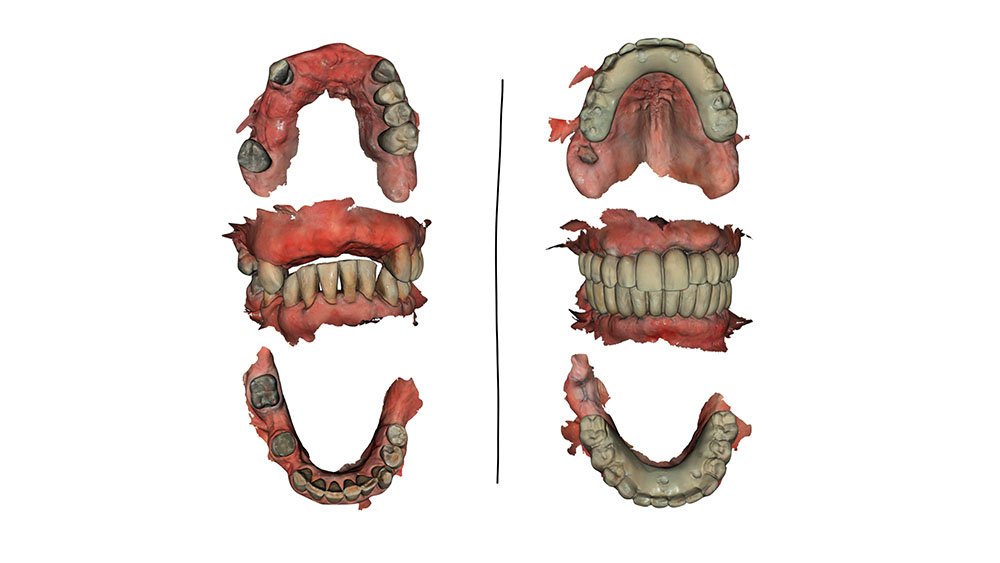

Prótese superior e inferior em resina acrílica.

Próteses provisórias. Na arcada superior, o tecido gengival será condicionado e na inferior, uma prótese dento-gengival será utilizada.

Condição inicial e atual, com próteses provisórias, através do escaneamento digital.

O corredor bucal foi corrigido antes da finalização da prótese provisória. Inicia-se a fase de avaliação das estratégias escolhidas para eventuais correções na prótese definitiva após 90 dias.